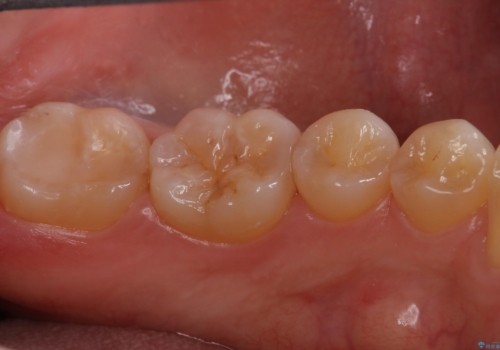

海外に引っ越す予定があり、見ため(審美性)強度ともに良い被せ物を希望されたため、セラミックインレーにて治療を行いました。

一部歯に保険治療で使用されている材料が劣化していたため、う蝕と一緒に取り除いて劣化の少ないセラミックに置き換わりました。